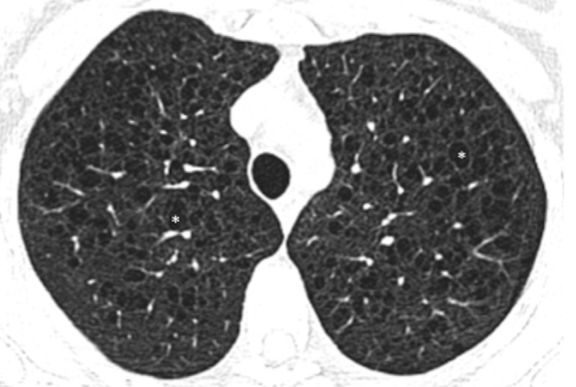

干燥综合征(SS)是不太容易鉴别诊断的,临床上因为干燥综合征引起肺部囊性改变的情况比较多,注意具有多种病理类型。

图:干燥综合征患者LIP + 淀粉样变